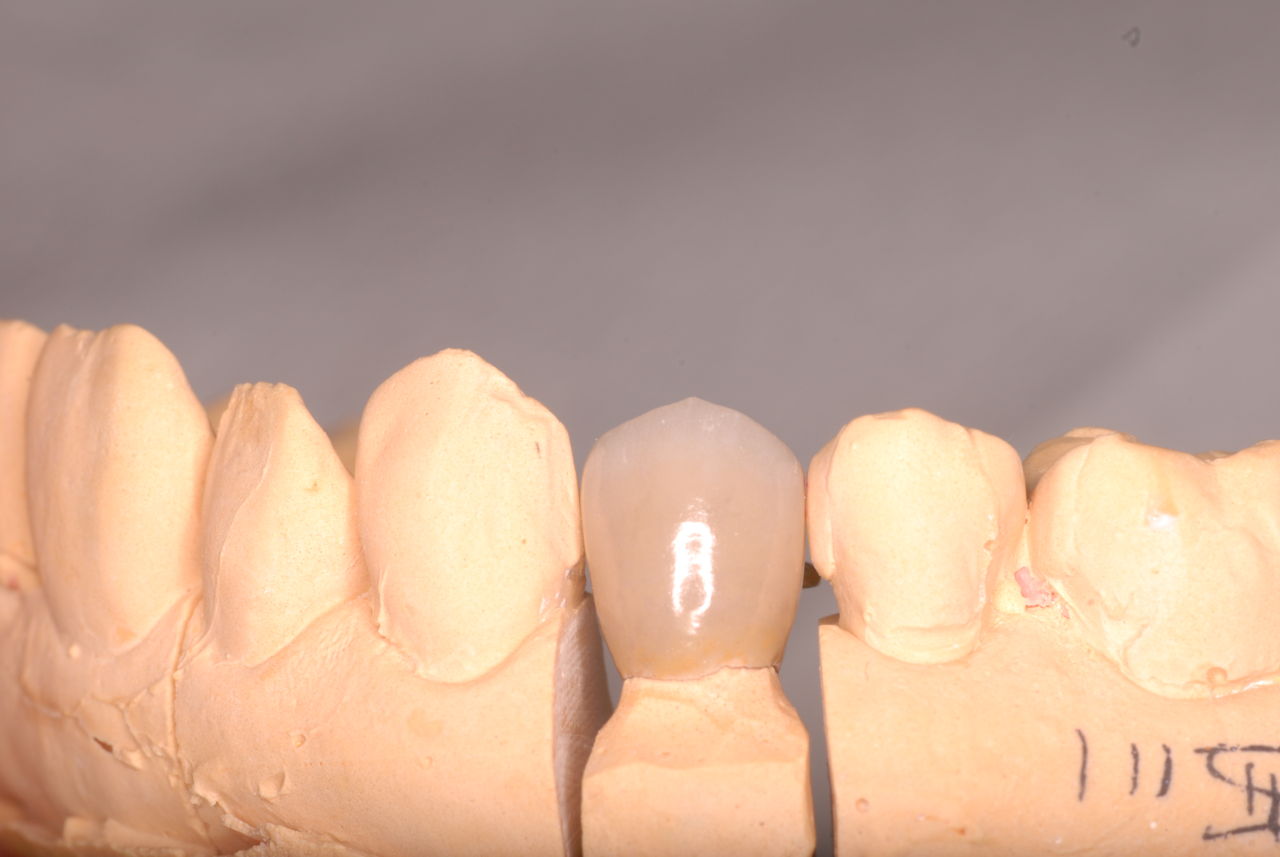

下記はかなりうまくいった方です。

平成9年治療、虫歯と神経の処置、歯周病の治療

2012,7月来院

欠けたところを埋めておしまいです。